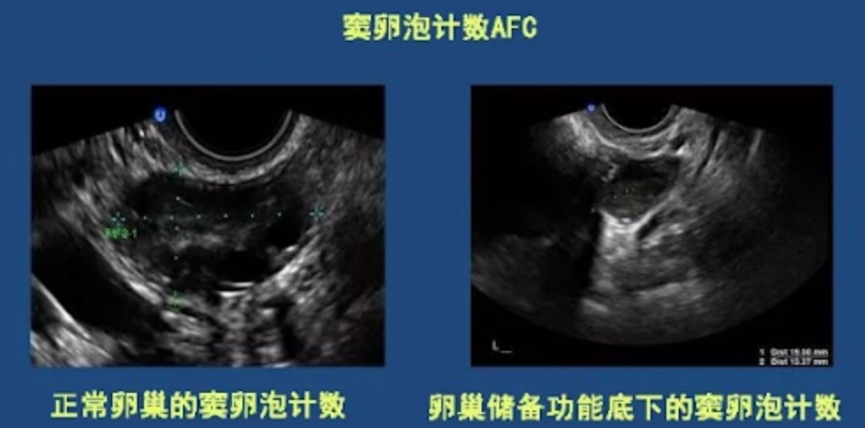

// AFC

AFC是指卵巢中窦卵泡数,是卵巢的储备功能指标之一,反映卵巢中可供产生成熟卵子的“种子”数量。阴道B超可以测量AFC以及卵巢的大小。

一般来说,卵巢功能衰退的患者双侧卵巢AFC总数小于6-8枚,此外,卵巢体积会明显缩小。